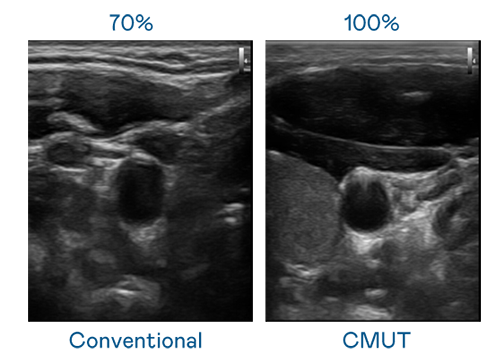

CMUT 技术是一种用电容式微机电元件来产生超音波讯号的技术。与传统 PZT 压电式技术相比,CMUT 频宽增加 30%,更宽频的超音波讯号让影像解析度大幅提升,是实现高影像品质医疗超音波扫描、促进精准医疗发展的关键技术。

大频宽带来超清晰影像

超音波影像的解析度高低,首先取决于探头能发出的讯号频宽。东升国际官网入口 CMUT 可提供高清晰的超音波讯号,提供高频宽、高灵敏度、影像纹理细节更高的超音波影像,协助医护人员缩短影像判读时间及利用精准的医疗影像进行诊断。